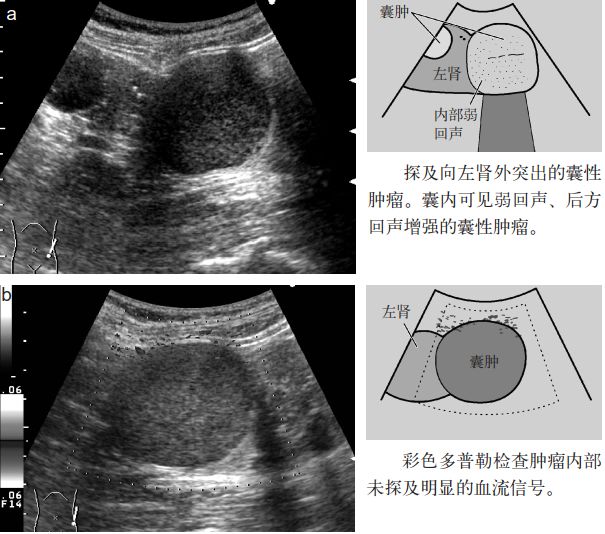

图4 肾囊肿(囊内出血)

图5 肾囊肿(囊内出血)

2.囊肿内出血时内部有回声,需要与囊肿内肿瘤鉴别。彩色多普勒检查可确认内部回声中有无血流信号。囊肿内出血时其内部无血流信号。